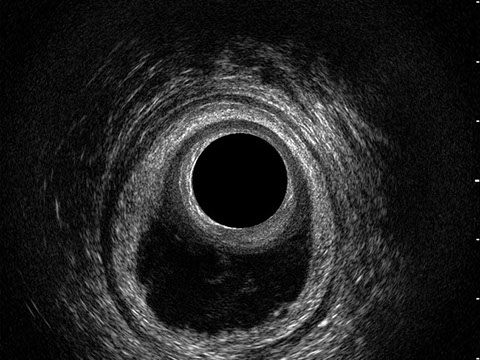

L’ecografia transanale è un esame diagnostico per immagini che consiste nell’introduzione di un trasduttore ad ultrasuoni. Le immagini qualitativamente migliori del canale anale sono ottenute usando un trasduttore rotante, montato in un manipolo rigido, che fornisce un’immagine a 360°. Con le apparecchiature più moderne è anche possibile ottenere immagini tridimensionali.

L’ecografia transanale permette di distinguere la sottomucosa che riveste il canale anale, lo sfintere anale interno, e lo sfintere anale esterno.